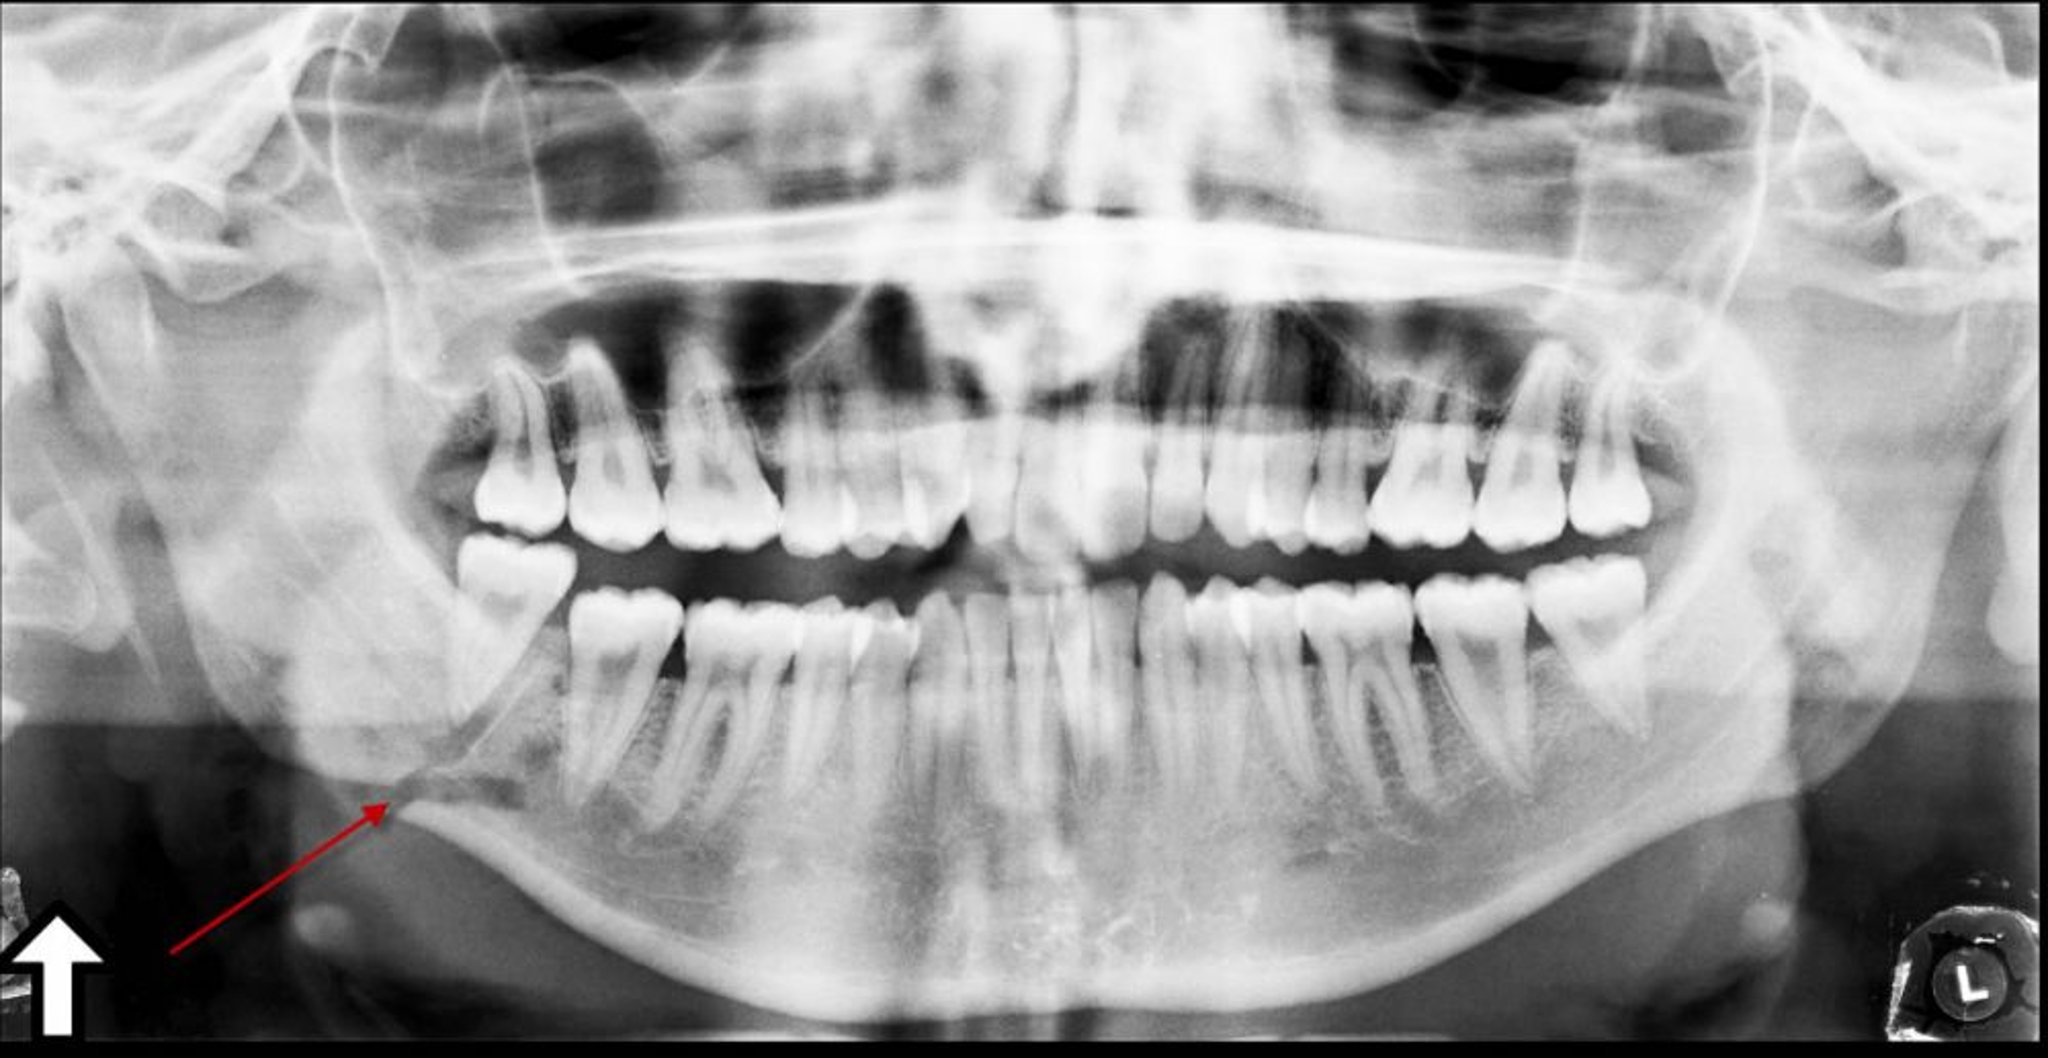

Панорамна рентгенографія зубів є найкращим методом дослідження при ізольованому переломі нижньої щелепи. Для діагностики переломів кісток обличчя проводять комп’ютерну томографію з тонкими зрізами (товщина зрізу 1 мм) в аксіальній і фронтальній площинах.